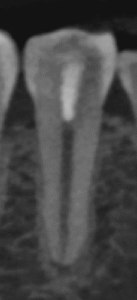

紹介患者さんの治療。

主訴は、

根管治療した歯が痛い…

Pre-op Endo test(2025.11.26)

#29に打診痛がある。

紹介元の先生によれば#40.04まで形成したが術後の痛みが続いているという。

根尖病変はない。

Pulp Dx: Previously initiated therapy

Periapical Dx: Symptomatic apical periodontitis

Recomended Tx: RCT

根管充填後にPA, CBCTを撮影した。

問題はないだろう。